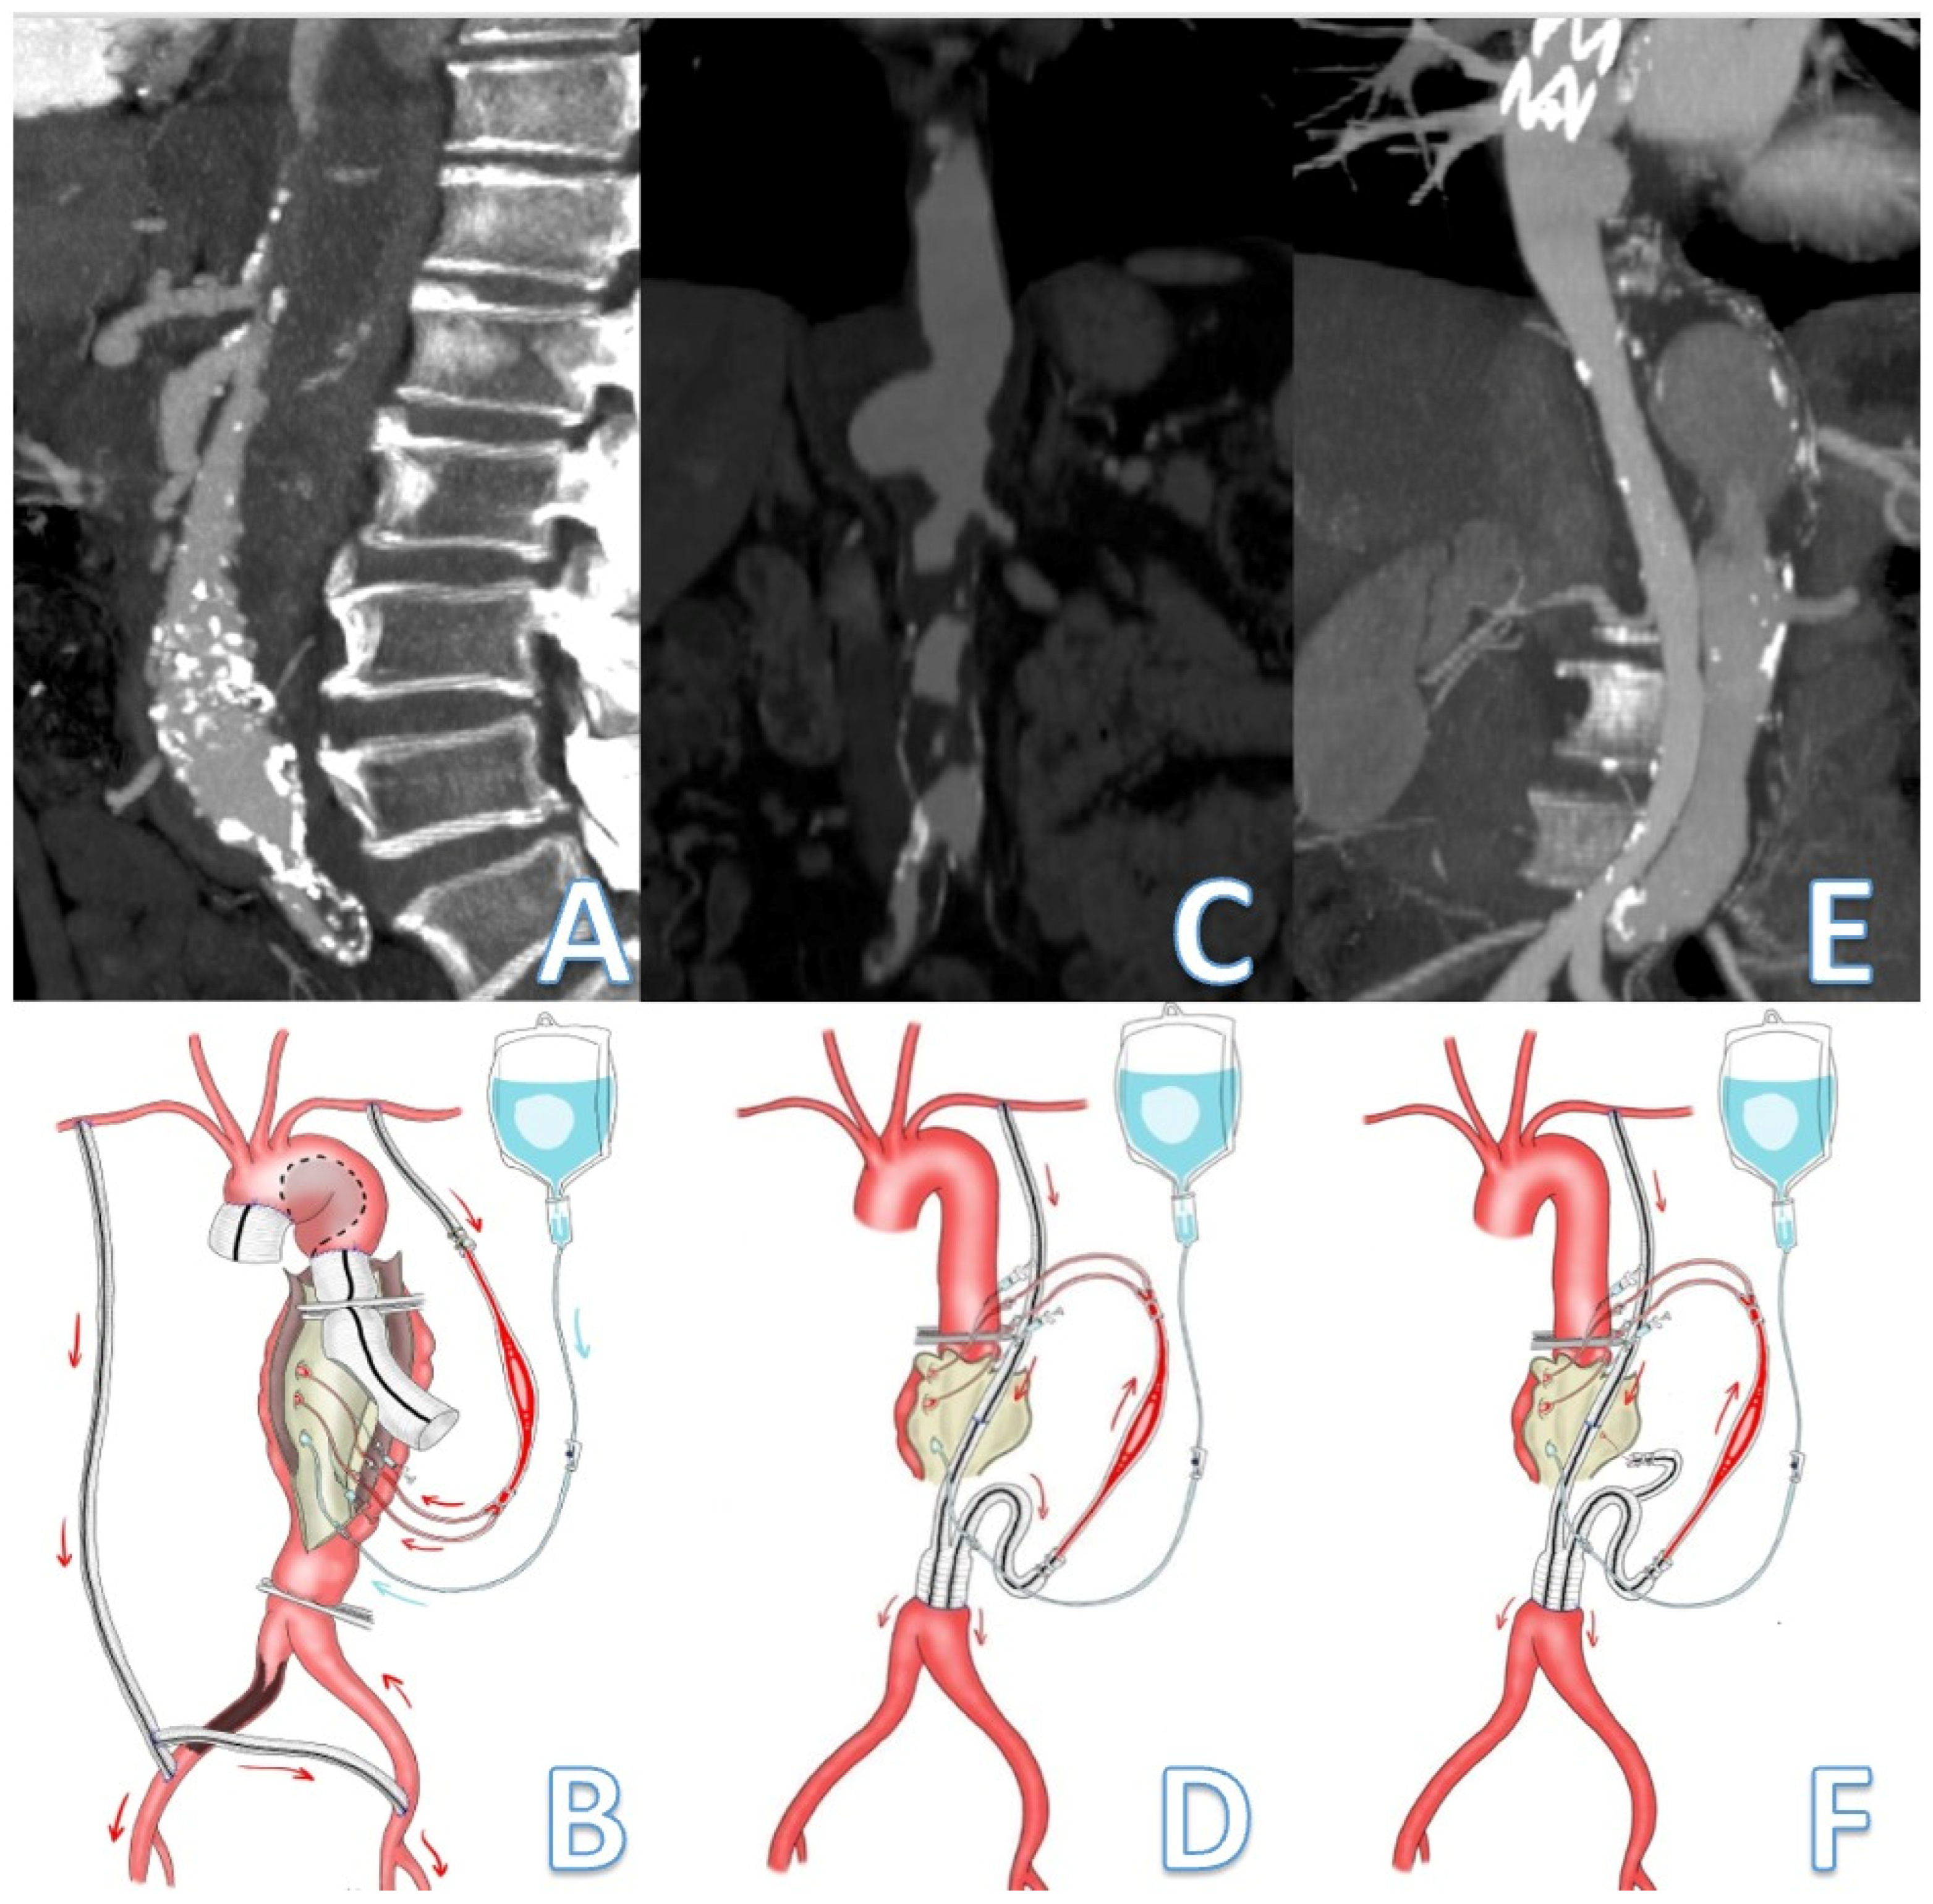

2.3. Passive Shunting: Surgical Technique